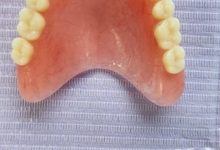

Clinica LUY ESTHETIC ART defineste parodontoza ca fiind rezultatul direct al placii dentare, care se depune pe suprafata dintilor, dar si in apropiere de marginea gingivala. Aceasta boala duce la pierderea dintilor, chiar daca ei sunt aparent sanatosi si nu prezinta carii. Edentatiile, afecteaza vorbirea, aspectul, dar si capacitatea de a mesteca.

Boala parodontala are un caracter progresiv. Pentru cazurile mai grave, recomandam tratamentul parodontal chirurgical rezectiv sau regenerativ.